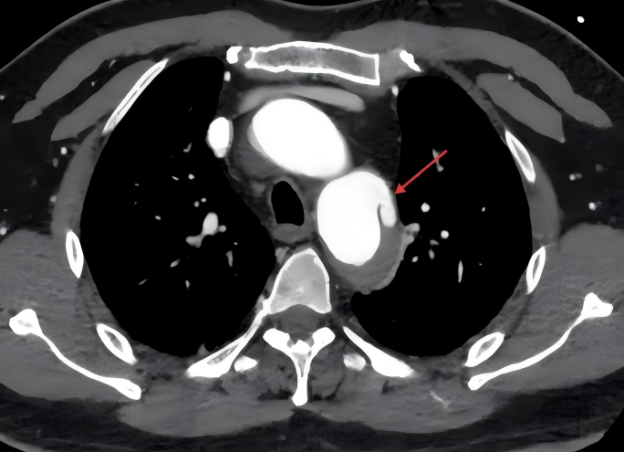

急诊增强CT检查证实了这一猜想:患者的胸主动脉血管内膜已被高速血流撕裂出一个破口,血流冲入血管壁中层。整个主动脉就像一根被过度充气、随时可能爆裂的水管,生命悬于一线。

增强CT显示主动脉壁内膜局部破裂,血流由破口处进入中膜